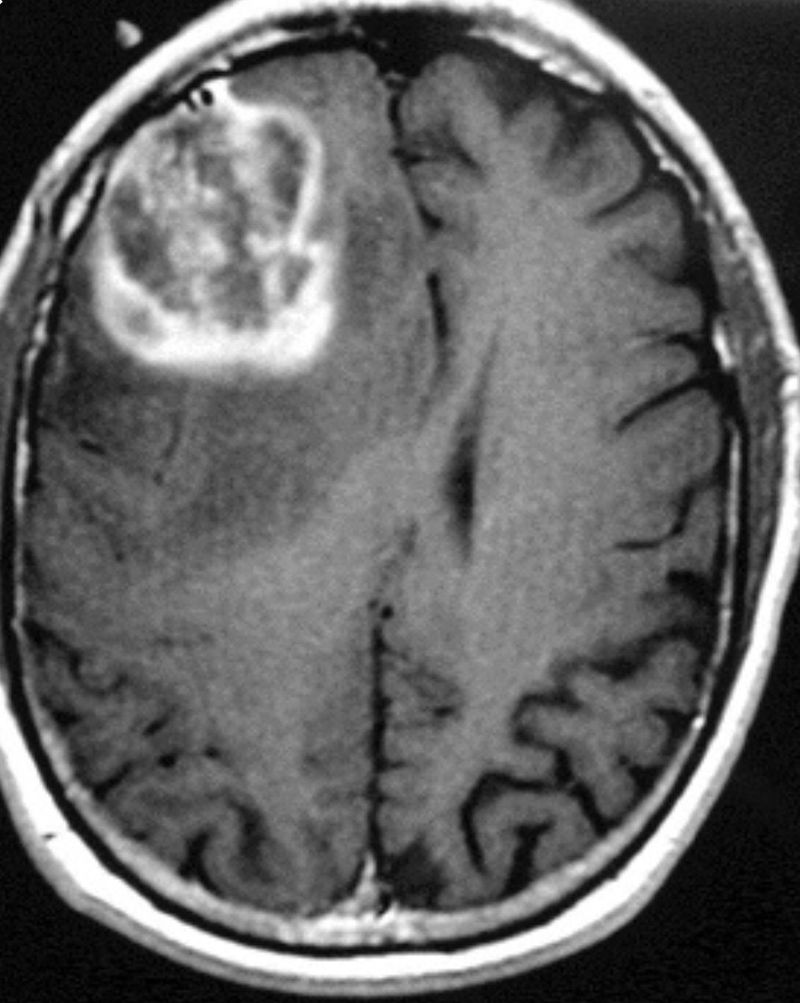

Imaging shows a large mass growing within the brain. After further observation, it was known to be GBM (Glioblastoma Multiforme). Unfortunately, GBM is not a benign tumor. It is a malignant one. It is a very aggressive and fast growing tumor. Even when neurosurgeons perform a craniotomy for the resection of a GBM, they may assign the patient to radiotherapy and chemotherapy.

This tumor is on the right frontal lobe (even though on the imaging it’s on the left side). Frontal lobe tumors have various symptoms. Some include impaired judgement, behavioral and emotional changes, sometimes papilledema, hemiplegia, etc. These might not always be the symptoms.

Will this tumor affect how the person functions? If so, what area will it affect?